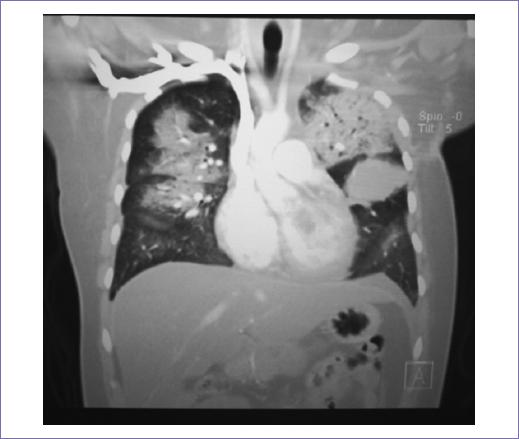

Recibió radioterapia adyuvante 50 Gy/25 fracciones, con técnica 3D conformal con campos tangenciales y axilosupraclavicular (Fig. 2); la toxicidad desarrollada durante el tratamiento fue radiodermitis grado I. Durante el seguimiento, siete meses después se documentó mediante tomografía con emisión de positrones dos nódulos pulmonares con hipermetabolismo, maximum standardized uptake value (SUVmax) 3.7 y 2.8, así como trombos en la vena pulmonar izquierda, arterias ilíacas comunes y externas. Un mes después, la paciente empezó con cefalea holocraneana con intensidad del dolor en escala visual analógica 8/10, por lo que se documentó con estudios de imagen una lesión intraaxial frontal izquierda de 50 x 42 mm, de características metastásicas (Fig. 3), motivo por lo que se consideró candidata a tratamiento quirúrgico, seguido de irradiación a holocráneo 30 Gy/10 fracciones (Fig. 4). Durante el último tratamiento presentó dificultad respiratoria súbita y se documentó tromboembolia pulmonar bilateral metastásica, motivo de fallecimiento (Fig. 5).

Al inicio de la presentación, el tamaño del tumor varía entre 0.5 y 40 cm3. El sarcoma del estroma mamario crece por invasión directa y su diseminación es hematógena, principalmente a pulmón, pleura, hígado (con menor frecuencia), médula ósea y cerebro. El involucro ganglionar axilar es muy raro, se presenta en menos del 5% de los pacientes y usualmente se presenta en etapas avanzadas9. En el caso reportado, la paciente presentó invasión local y hematógena cerebral y pulmonar.